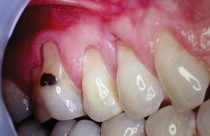

AVANT :

La greffe gingivale est recommandée par notre praticien de la Clinique Crillon à Lyon notamment dans le cas où il y a une récession de la gencive couramment appelé "déchaussement".

Cette intervention permet de préserver la gencive existante et d’arrêter la progression de la récession gingivale.

Une greffe gingivale est une chirurgie qui consiste à prélever un greffon (petit morceau de gencive) généralement du palais afin de l’apposer au niveau de la gencive, là où il y a un manque. Le tout est maintenu en place par un pansement parodontal, au besoin.